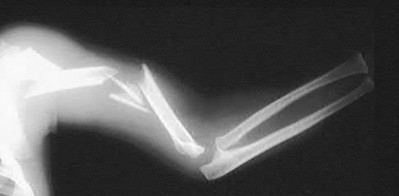

Figure A shows a radiograph of a 19-year-old male with an isolated shotgun injury. On physical examination, he has a 3 cm wound over the posterolateral aspect of his arm. In addition, he has weakness with wrist and finger extension, but no sensory deficits. The patient has received tetanus prophylaxis and antibiotics in the emergency department. What would be the next best steps in treatment?

This patient has sustained a shotgun blast to the midshaft humerus. The next best step would be irrigation and debridement, and external fixation of the fracture.

Shotgun injuries are typically treated as open fractures, whereas low-energy gunshot wounds are treated as closed fractures. The initial operative treatment of shotgun wounds should include irrigation and debridement and stabilization with external fixation. The goal of treatment is to stabilize the severe soft-tissue injury and bone loss, as well as to aggressively debride devitalized tissue and gross contamination.

Dougherty et al. reviewed gunshot fractures to the humerus. They report that

peripheral nerve injuries are relatively common with these injuries, with a more common incidence in distal injuries than proximal.

Joshi et al. looked at low velocity gunshot fractures to the humerus. They found that these injuries can be safely treated as closed fractures with local wound care, fracture brace and oral antibiotics. The time to union was similar in the non-operative and open treatment group.

Berick et al. examined the indications for nerve exploration with humerus gunshot fractures. They recommend continued observation of isolated nerve palsies associated with gunshot fractures of the humerus. However, consider early nerve exploration of palsies when associated with a concomitant vascular injury.

Figure A shows a high velocity shotgun fracture to the left humerus with retained buck fragments. Illustration A shows a similar injury stabilized with external fixation.

Incorrect Answers:

Answer 1: Due to the severity of soft tissue injury, external fixation should be considered for initial stabilization. Vascularized fibular grafts has been expanded to an osteoseptocutaneous flap by including a cutaneous flap on the lateral aspect of the lower leg. These are not typically used in the acute setting.

Answer 3: Retrograde intramedullary nail would not be the ideal implant for this injury, acutely.

Answer 4 and 5: There is no indication for a CT scan or prolonged antibiotics. The fracture and soft-tissue injury should be initially stabilized with external fixation. Coaptation splinting will interfere with soft tissue care.